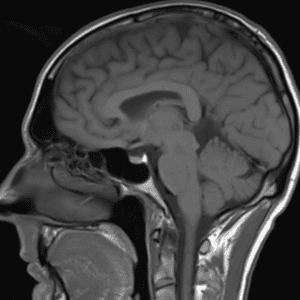

Case #43

Secondary CNS lymphoma